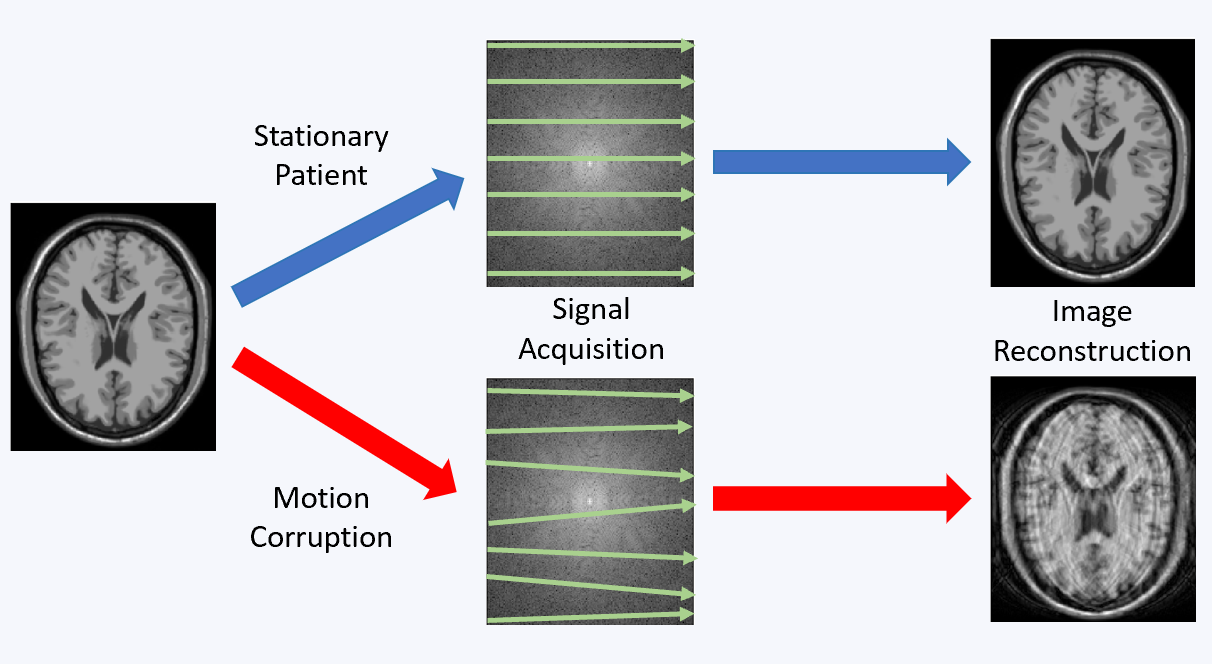

Magnetic resonance imaging (MRI) offers a unique opportunity to non-invasively study the human brain, equipped with a wealth of contrasts (to disentangle structures and functions), and a favourable window of spatiotemporal resolution. But to expand its clinical and neuroscientific scope, MRI has to become faster and more robust. A key ingredient to this end is a mechanistic understanding of the imaging physics, and its consideration in the way we acquire and reconstruct MR images. This comprises the choice of optimal sequence and sampling strategy for the target application (e.g., spiral trajectories for short echo-time) a detailed characterization of both hardware imperfections (e.g., heating/field drift and trajectory errors) and subject-related noise sources (e.g., breathing, motion) giving rise to image artifacts, the accurate inclusion of this information into an expanded signal model of the MR imaging process and advanced image reconstruction techniques capable of inverting these intricate models. This integrated approach leads to better imaging data tailored to the analysis and diagnostic purpose of the MR exams. The characterization of each scan’s imaging peculiarities allows for better comparability of multi-site studies in the era of big data. At the other end of the spectrum, personalized medicine requires individualized MR imaging protocols that are enabled by flexible and extendable signal models and reconstructions.